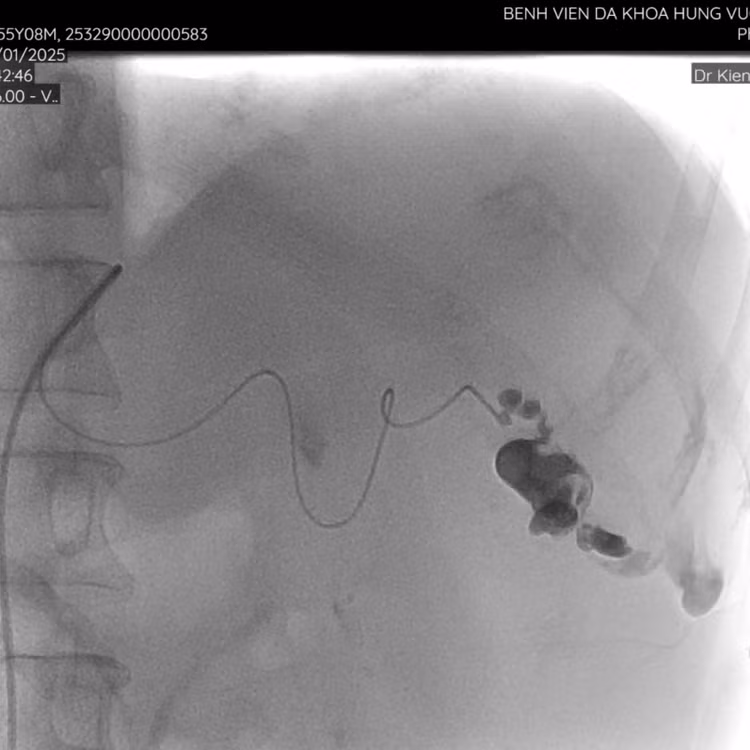

| Thăm khám cho bệnh nhân sau can thiệp - Ảnh BVCC |

Hiện tại, sau gần 5 ngày can thiệp sức khỏe bệnh nhân đã tiến triển tốt, mạch, huyết áp ổn định, được ra viện và theo dõi tình trạng sức khỏe tại nhà.

Theo Thạc sĩ, bác sĩ Trần Văn Kiên, Phó Trưởng khoa Chẩn đoán hình ảnh chia sẻ: lách là tạng đặc dễ vỡ nhất khi bị chấn thương và tiến triển nhanh dẫn đến sốc mất máu nguy cơ tử vong cao, nút mạch cầm máu là thủ thuật xâm lấn tối thiểu giúp cầm máu nhanh, bảo tồn được lá lách trong trường hợp vỡ lách độ IV/V huyết động ổn định.